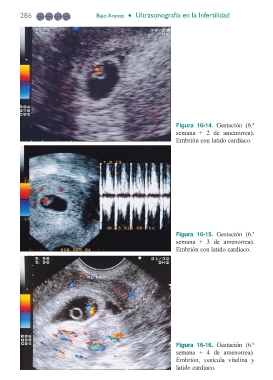

Figura 16-14. Gestación (6.ª

semana + 2 de amenorrea).

Embrión con latido cardiaco.

Figura 16-15. Gestación (6.ª

semana + 3 de amenorrea).

Figura 16-16. Gestación (6.ª

semana + 4 de amenorrea).

Embrión, vesícula vitelina y

latido cardiaco.